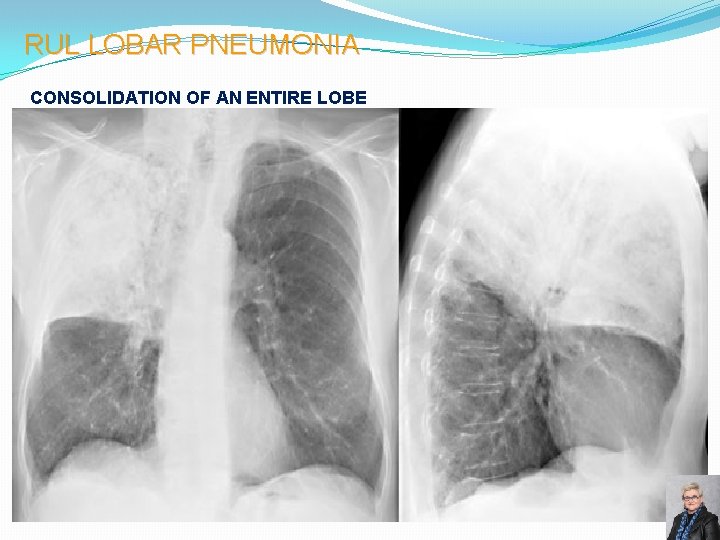

RUL LOBAR PNEUMONIA CONSOLIDATION OF AN ENTIRE LOBE 58